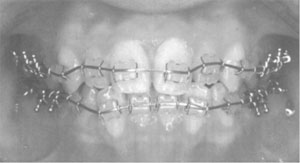

1歯医者さんでは、虫歯の治療に金・銀・パラジウム合金やコバルト・クロム合金を溶かして精密に固めて、欠けた部分の補填やブリッジに使用しています。歯並びを良くするための歯列矯正ワイヤには、 伸び縮みしやすい(弾性といいます。)ニッケル・チタン合金が使用されています。ニッケル・チタン合金には、超弾性という性質があるため、歯をじわじわと押して歯並びをよくします。また、なくなった歯に代わる人工歯根(インプラント)にはチタン合金が使用されています。

<歯列矯正ワイヤ(超弾性Ti-Ni合金)(日本金属学会編:医療用金属材料概論,(丸善,2011),p39)>HP